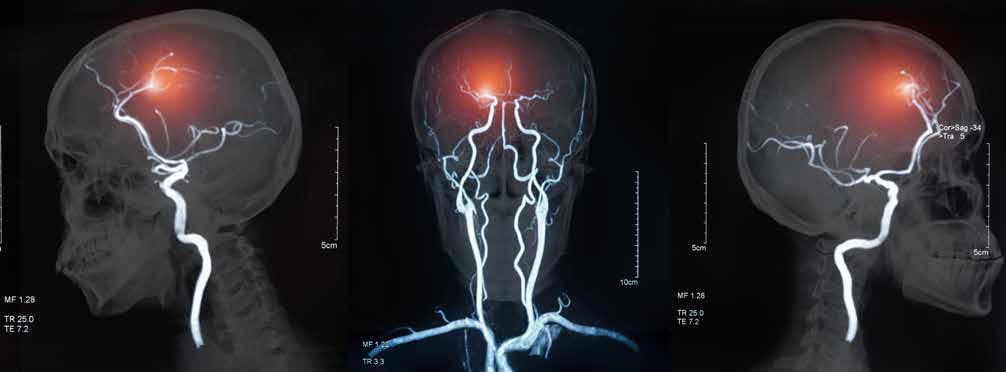

sometimes called brain attacks, are the third leading cause of death in Texas. For anyone experiencing a stroke, time is the most critical factor. Imagine if a stroke happened to a loved one, and you were alone with them. Would you know what to do?

A stroke occurs when the blood supply to the brain is blocked or when a blood vessel in the brain bursts. This can quickly damage brain cells and is a medical emergency. Depending on which parts of the brain are affected, the common signs of a stroke include: